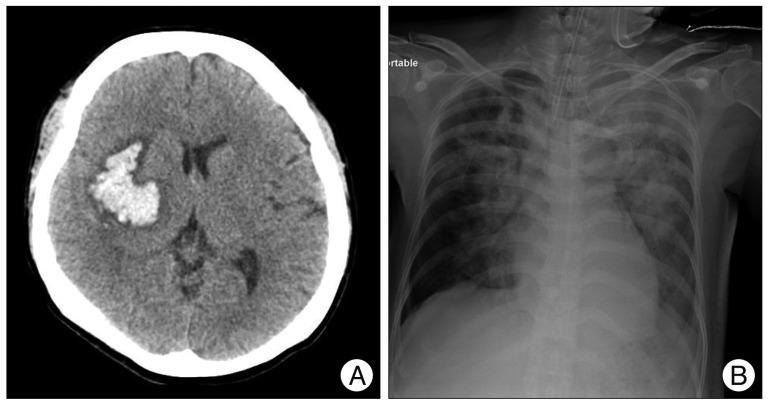

Tracheoinnominate artery fistula is a critical complication of tracheostomy. The most important factors influencing patient outcome are prompt diagnosis, immediate control of bleeding with a patent airway, and emergency operation with or without interruption of the innominate artery. Here, we report a case of tracheoinnominate artery fistula in a 40-year-old woman with cerebrovascular accident who was successfully managed with an aorta-axillary artery bypass.

气管无名动脉瘘是气管切开术的一种严重并发症。影响患者预后的最重要因素是及时诊断、在气道通畅的情况下立即控制出血以及对无名动脉进行或不进行阻断的急诊手术。在此,我们报告一例40岁脑血管意外女性患者发生气管无名动脉瘘的病例,该患者通过主动脉-腋动脉旁路移植术成功得到治疗。